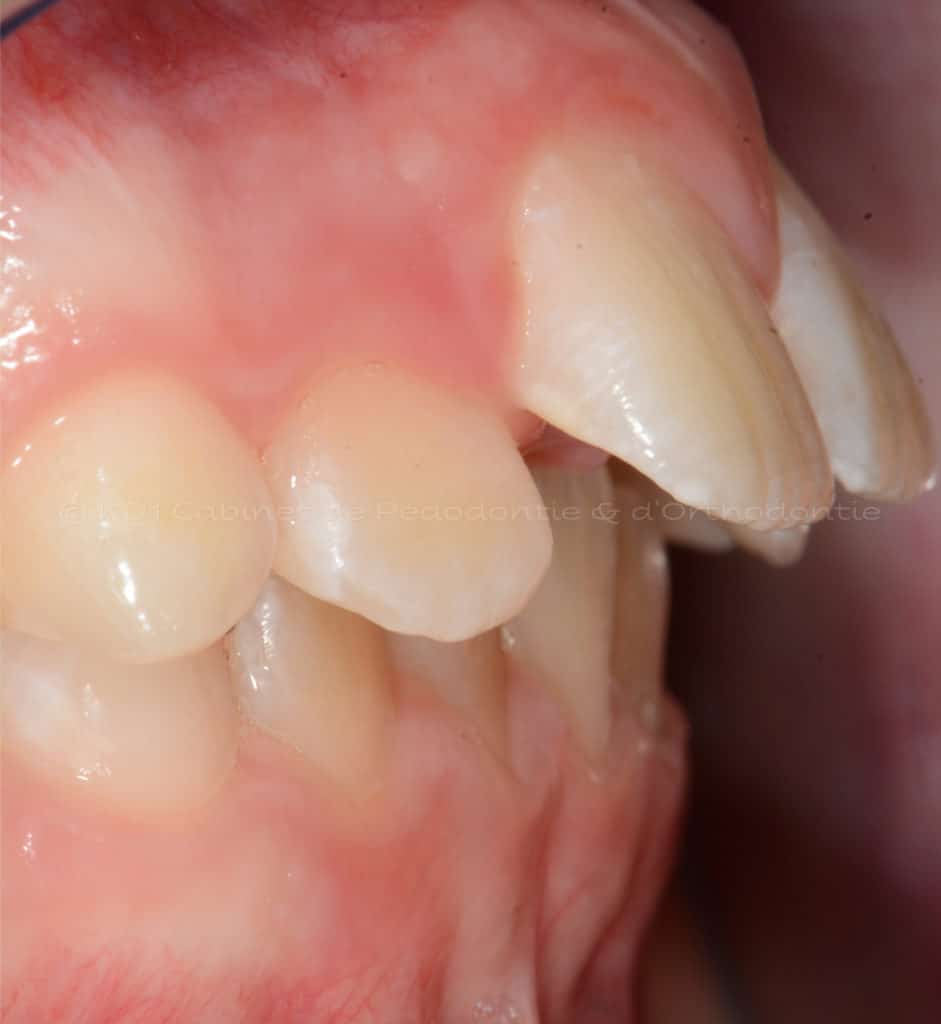

Cas #1 – Traitement avec des bagues, deuxièmes prémolaires et dent de sagesse supérieures ectopiques.